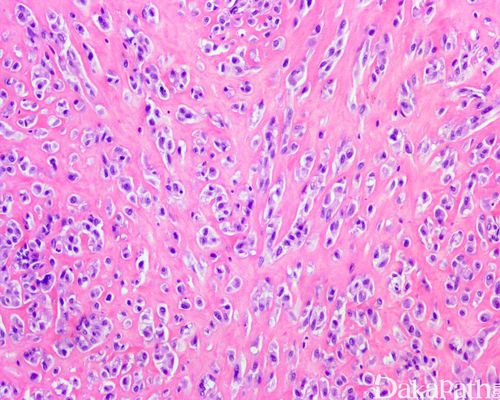

骨肉瘤切片

骨肉瘤切片,骨肉瘤图片